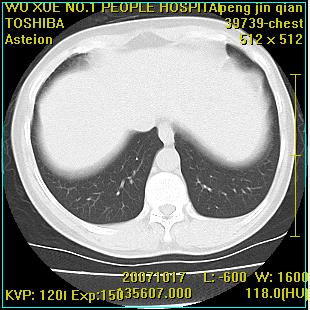

标题: CT10148:男,56岁,咳血。 [打印本页]

标题: CT10148:男,56岁,咳血。

左肺上叶尖段占位性病变,考虑肺癌.癌性空洞,并双肺转移灶及纵隔淋巴结转移

左肺上叶尖后段较大团块影,边缘光滑,内见不规则裂隙样空洞,周围明显见细小结节及渗出,与肺门方向结构紊乱,另:左上叶尖段外侧 舌叶内侧 右上叶尖段及下叶背段均见片状致密影。考虑:继发性肺结核伴空洞形成!

左上肺厚壁空洞影、两肺多发小片样不规则高密度灶。基本上能排除转移瘤。考虑肺结核伴空洞形成。

左上肺后壁空洞,内壁不规则,可见壁结节;左上叶尖段外侧 舌叶内侧 右上叶尖段及下叶背段均见片状致密影。考虑:左肺肺癌并两肺继发性肺结核?

左肺上叶尖后段较大团块影,边缘光滑,内见不规则裂隙样空洞,周围明显见细小结节及渗出,与肺门方向结构紊乱,另:左上叶尖段外侧 舌叶内侧 右上叶尖段及下叶背段均见片状致密影。考虑:继发性肺结核伴空洞形成!建议进一步检查,除外肺癌

右肺下叶背段/左上肺/左下肺结核伴空洞形成

结核 空洞伴两肺播散

浸润型肺结核伴左上肺空洞形成,两肺播散灶